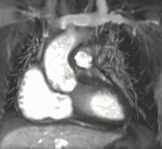

Partial Anomalous Pulmonary Venous Drainage by CMR